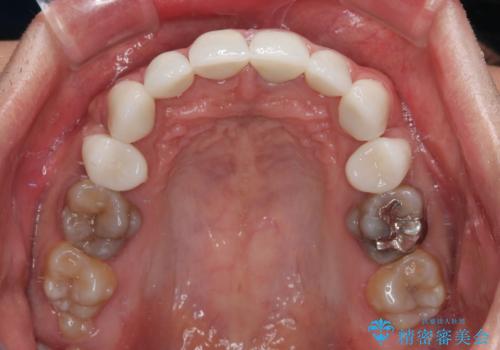

- 口元の突出感を改善するための抜歯矯正を終えた患者様ですが、幼少期からの変色した歯をセラミッククラウンにて自然な色合いに変えていくこととしました。

口を開けたときに目につく範囲を希望されたため上下ともに8本ずつをオールセラミッククラウンによる補綴治療を行うこととしました。

近年では大変珍しいですが、胎児あるいは乳幼児期の抗生物質の影響で永久歯が変色してしまうことがあります。

ホワイトニングでの改善は期待できないため、オールセラミッククラウンによる補綴治療が必要となります。